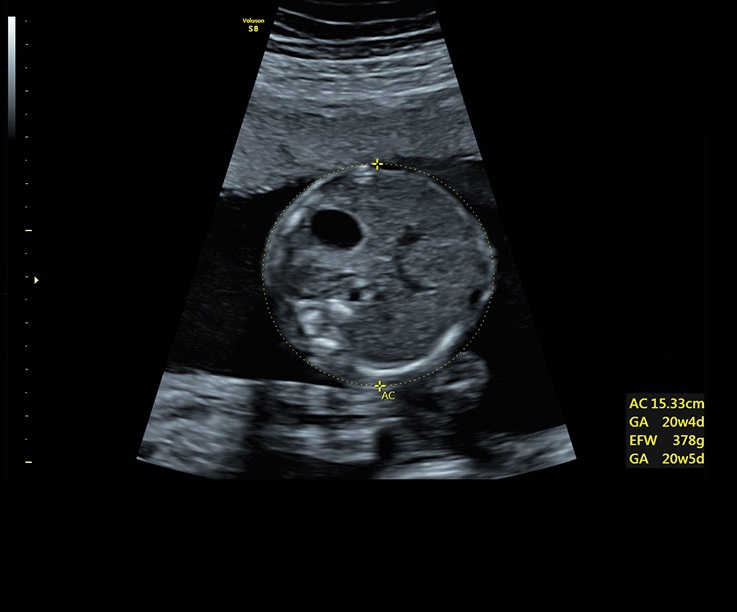

• Технология автоматической фетометрии в 2D режиме (SonoBiometry): Эта технология позволяет автоматически измерять бипариетальный размер, окружность головы, окружность живота, длину бедра и плеча плода, обеспечивая точные и надежные измерения.

Все эти технологии на ультразвуковом сканере Voluson S8 способствуют улучшению точности диагностики, облегчению процесса измерений и получению детальных изображений для более полного понимания состояния плода.

• Автоматический расчет толщины воротникового пространства SonoNT и размера четвертого желудочка SonoIT

• SonoBiometry (автоматическое измерение BPD, AC, HC, HL, FL)